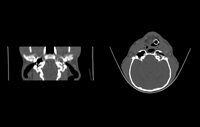

Cavités Nasales

- Jetage et Rhinite Chronique (nez qui coule)

- Epistaxis (saignements de nez)

- Déformations et douleurs du chanfrein (museau)

- Eternuements récurrents, "Reverse sneezing"

- Suspicion d'Aspergilose, de tumeur ou de corps étranger dans les fosses nasales.

- Sinusites